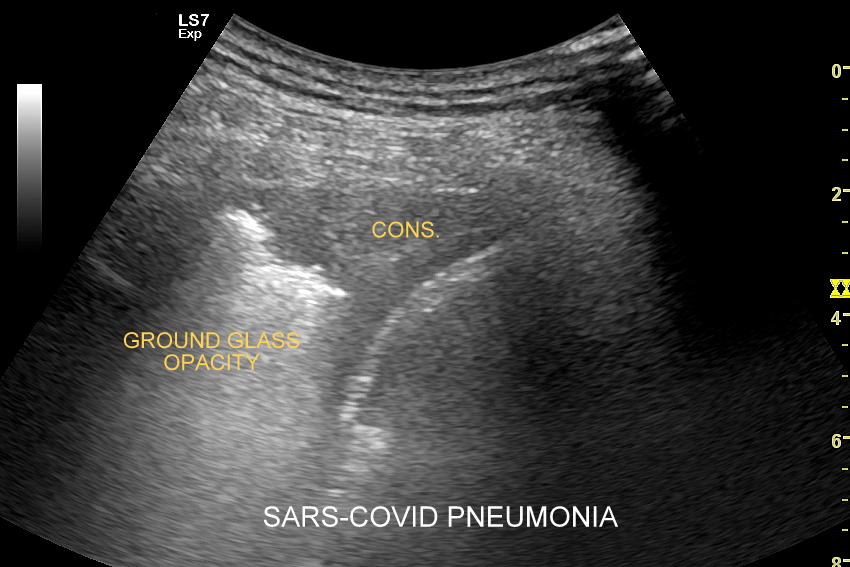

Ultrasonografia płuc oparta jest o fizykę fal akustycznych. Wychwytuje zarówno schorzenia lokalizujące się w zewnętrznych partiach płuc oraz w jamach opłucnowych w postaci realnego obrazu, ale także wykazuje istotne diagnostycznie informacje z głębszych partii narządu na podstawie specyficznych artefaktów generowanych przez patologie wewnątrz płuca.

Kluczem do wartościowego zastosowania metody USG w diagnostyce pulmonologicznej jest zrozumienie jej możliwości oraz ograniczeń. USG jest niezwykle czułym badaniem w diagnostyce zapaleń płuc zarówno płatowych, jak i atypowych, np. wywołanych przez Mycoplasma lub Chlamydia. W przypadku zapalenia płuc pojawienie się widocznych zmian sonograficznych wyprzedza wystąpienie fenomenów osłuchowych wykrywanych przy osłuchiwaniu klasycznym stetoskopem. Metoda USG jest również bardzo czuła w diagnostyce chorób opłucnej i jam opłucnowych, takich jak nowotwory opłucnej, odma odma opłucnowa czy płyn w jamie opłucnowej. W rękach doświadczonego lekarza badanie USG może być przydatne w wykryciu zatorowości płucnej, a nawet guzów nowotworowych płuc.